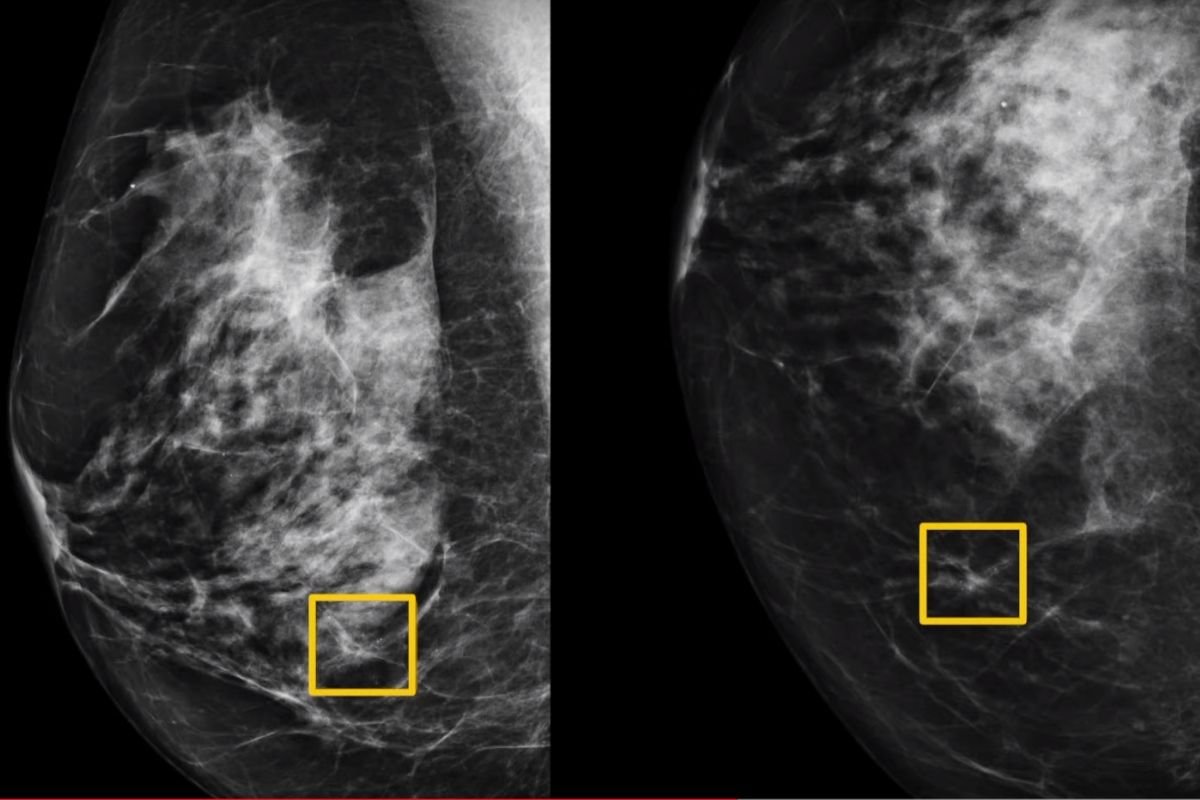

Badania sugerują, że sztuczna inteligencja jest dokładniejsza w diagnozowaniu raka piersi na podstawie badań mammograficznych niż radiolodzy. Google Health właśnie zakończył z sukcesem testy przeszkolonego przez siebie algorytmu. Niebawem system może wspomóc lekarzy we wczesnym wykrywaniu raka piersi.

Międzynarodowy zespół ekspertów, w tym naukowcy z Google Health, Cancer Research UK Imperial Center, Northwestern Uniwesity i Imperial College London, stworzył system sztucznej inteligencji, który tylko na postawie badań mammograficznych dokładnie przewiduje to, czy kobieta ma raka piersi.

Jak czytamy w Nature, algorytm przeszkolono na podstawie zdjęć rentgenowskich prawie 29 tys. kobiet, a jego wydajność porównano z decyzjami podejmowanymi przez specjalistów podczas wizyt przesiewowych.

Okazało się, że radził sobie lepiej niż radiolodzy – wykazał bezwzględną redukcję wyników fałszywie dodatnich, tzn. kobiet nieprawidłowo skierowanych do dalszego badań. Każde zdjęcie analizował na aż trzy sposoby. W efekcie czytał mammogramy tak dobrze, jak dwóch pracujących razem radiologów.